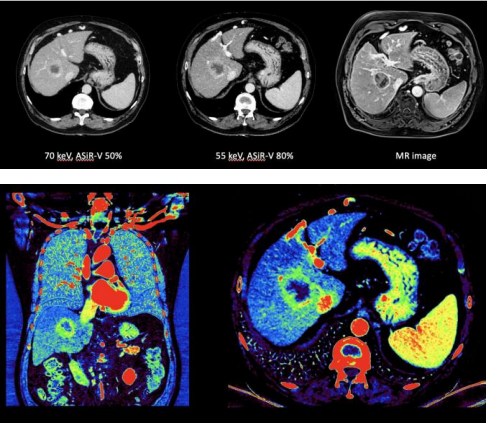

能谱的出现突破了CT的边界,常规CT只有单一的CT值这一参数,而能谱成像能够通过一次扫描就获得包括基物 质图像、单能量图像、虚拟平扫图像、有效原子序数等多参数图像。能谱CT可以发现传统CT难以发现的病灶,作出更精确的良恶性定性诊断,并可以进行物质成分的定量分析。高低压瞬切技术是GE独有的实现能谱成像的方式,140kv和 80kv高低两组电压在0.25ms的瞬间内进行切换,保证了信号源的一致,排除其他因素干扰。APEX CT在高低压瞬切技术之后,再次突破了能谱技术的最高挑战,实现了电流随着电压同步瞬间切换的双瞬切技术,这种电流调节的时间精度是从未达到的新高度,比任何模拟化电子束调节技术都要快 2000倍;kv/ma同步双瞬切的技术突破了能谱扫描是低能量采集信号强度不足的瓶颈,能谱信号中高低能量的分布更加均匀,从而使能谱成像中无论是低能量成像、虚拟平扫图像和基物质图像的质量都有了一个质的飞跃,达到了类MR的对比度。

细胞肝癌假包膜征,70KEV, 50KEV 单能量和 MR 图像对比;碘图中显示中间深蓝色是已经坏死的肿瘤细胞,周边绿色的是生长中的肿瘤组织,红色的是肿瘤血供,肿瘤周边正常肝组织 呈现低灌注,营养不良,长期发展会导致肝硬化。